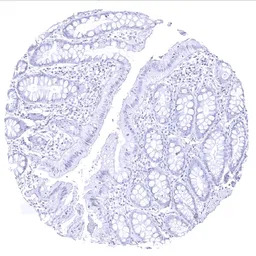

IHC-P analysis of human rectum mucosa tissue section using GTX04365 Thyroglobulin antibody [MSVA-189R] HistoMAX.